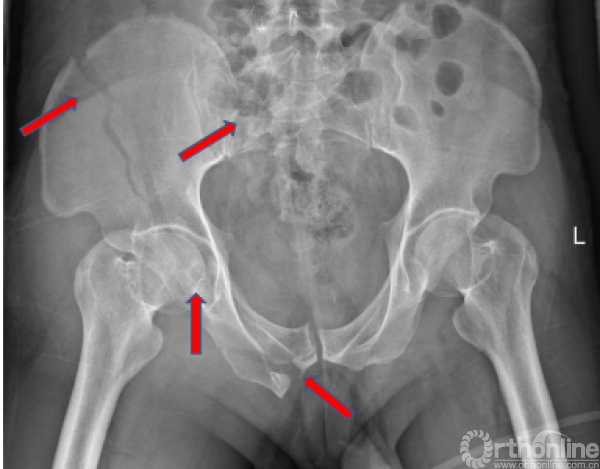

术前X线(2017.09.17)

骨盆正位、骨盆入口位、骨盆出口位

骨折的正确分型

骨盆AO和Tile分型,以及基于骨折的受伤机制和稳定性Young and Burgess分型:APC LC(lc-II型)、VS、CM;髋臼两类十型(前柱合并前壁);骶骨骨折Dennis分型(II区)

骨折移位方向的准确判断(五种+混合)

基本类型:上移、外翻、内翻、旋前、旋后;以及混合型